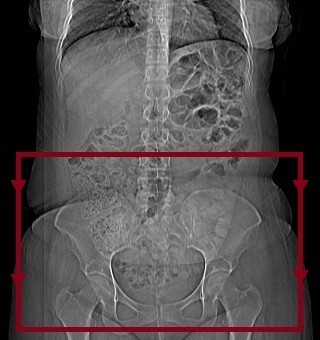

Alt Abdomen BT Çekim Tekniği

Kesitler aksiyal plana paralel olmalıdır.Bu nedenle açısız çekilir.Tarama alanı böbrek bitiminden ( crista-iliaka seviyesinin birkaç cm üstünden ) başlayarak simfisiz pubis bitene kadar devam eder. Eğer hastada rektumla ilgili bir rahatsızlıktan şüpheleniliyorsa ( örneğin rektum CA ) tarama alanı pelvis bitiminden birkaç cm aşağıya kadar devam ettirilmelidir. Rutinde kontrastlı çekim yapılmakla birlikte isteğe bağlı olarak kontratsızda çekilebilir. Kontrastlı çekimlerde rutinde intravenöz ve oral kontrast kullanılmakla birlikte bazı özel durumlarda sadece intravenöz yada sadece oral kontrastda kullanılabilir. Oral kontrast suyun içine kontrast madde katılarak hazırlanır.Hasta aç karnına ve bağırsak boşaltımı yapılmış olmalıdır.Hastadan hazırlanan sudan beş dakikada bir bardak içerek oral kontrastı tamamen bitirmesi söylenir.Hasta oral kontrasti içtikten sonra idrarına iyice sıkışana kadar çekime alınmaz. Rutinde film basımı mediasten penceresinde yapılmakla birlikte travma,kemik dejenerasyonu yada kanser söz konusu ise kemik pencereside basılır.

Alt Batın BT Aksiyal - Alt Abdomen BT Aksiyal